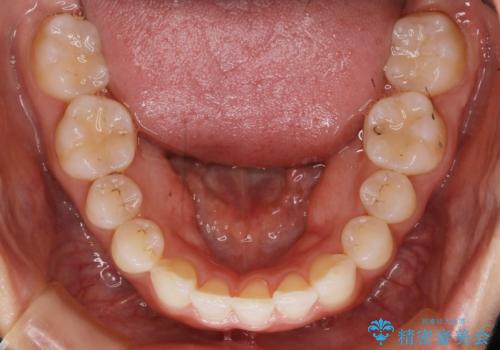

【非抜歯】下の前歯が1本少ない場合の矯正治療

- 前歯のガタつきを主訴に来院されました。

生まれつき下の前歯が1本少なく、その分のスペースを上の前歯がガタつくことで埋めているという状況でした。

上下それぞれのガタつきをとっていく過程で、歯1本分のスペースの差を、上顎の前歯のIPRで調整して並べる方法をご提案させていただきました。